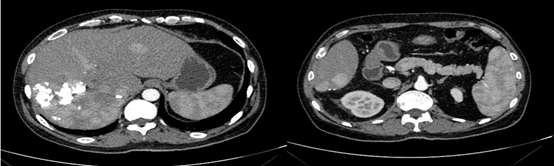

2018-12-11腹部CT检查提示,肝硬化、脾略大、门静脉高压;肝S6占位性病变,考虑原发性肝癌;肝S7段2枚结节;肝多发小囊肿,肝右叶钙化灶;双肾囊肿。

图片

图:腹部CT检查(2018-12-11)